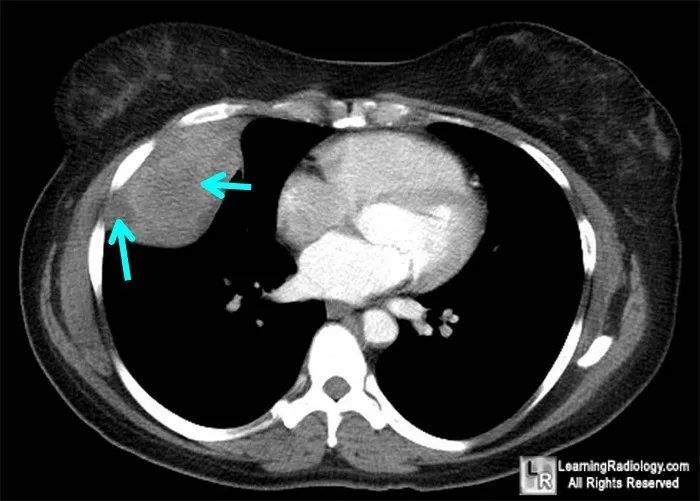

右上后部胸膜肿块,肿瘤内见脂肪密度,肿瘤无明显强化.

胸膜恶性肿瘤考虑转移瘤